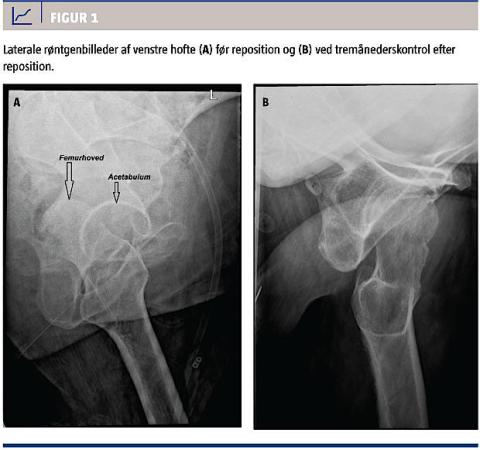

En objektiv undersøgelse viste forkortning og indadrotation af venstre underekstremitet. Således var der klinisk mistanke om brud på lårbenshalsen, men anterior-posterior-røntgenoptagelser viste ingen tegn på fraktur, hvorimod en lateral optagelse viste bagre luksation af venstre hofte (Figur 1A). Der blev foretaget lukket reposition af hofteleddet med opnåelse af normal længde og stilling af venstre underekstremitet. En kontrolrøntgenskanning og CT efter reposition bekræftede hofteleddets anatomiske stilling, dog med en mindre avulsion af den bagerste kant af acetabulum, hvilket blev behandlet konservativt. Patienten påbegyndte genoptræning hos en fysioterapeut på hospitalet og kunne tåle fuld vægtbelastning under træningen.

Ved den sidste opfølgende kontrol (tre måneder senere) havde patienten ingen smerter eller ubehag fra venstre hofteled ved daglige aktiviteter. Et røntgenbillede af hoften viste normale forhold uden tegn på avaskulær caputnekrose (Figur 1B).